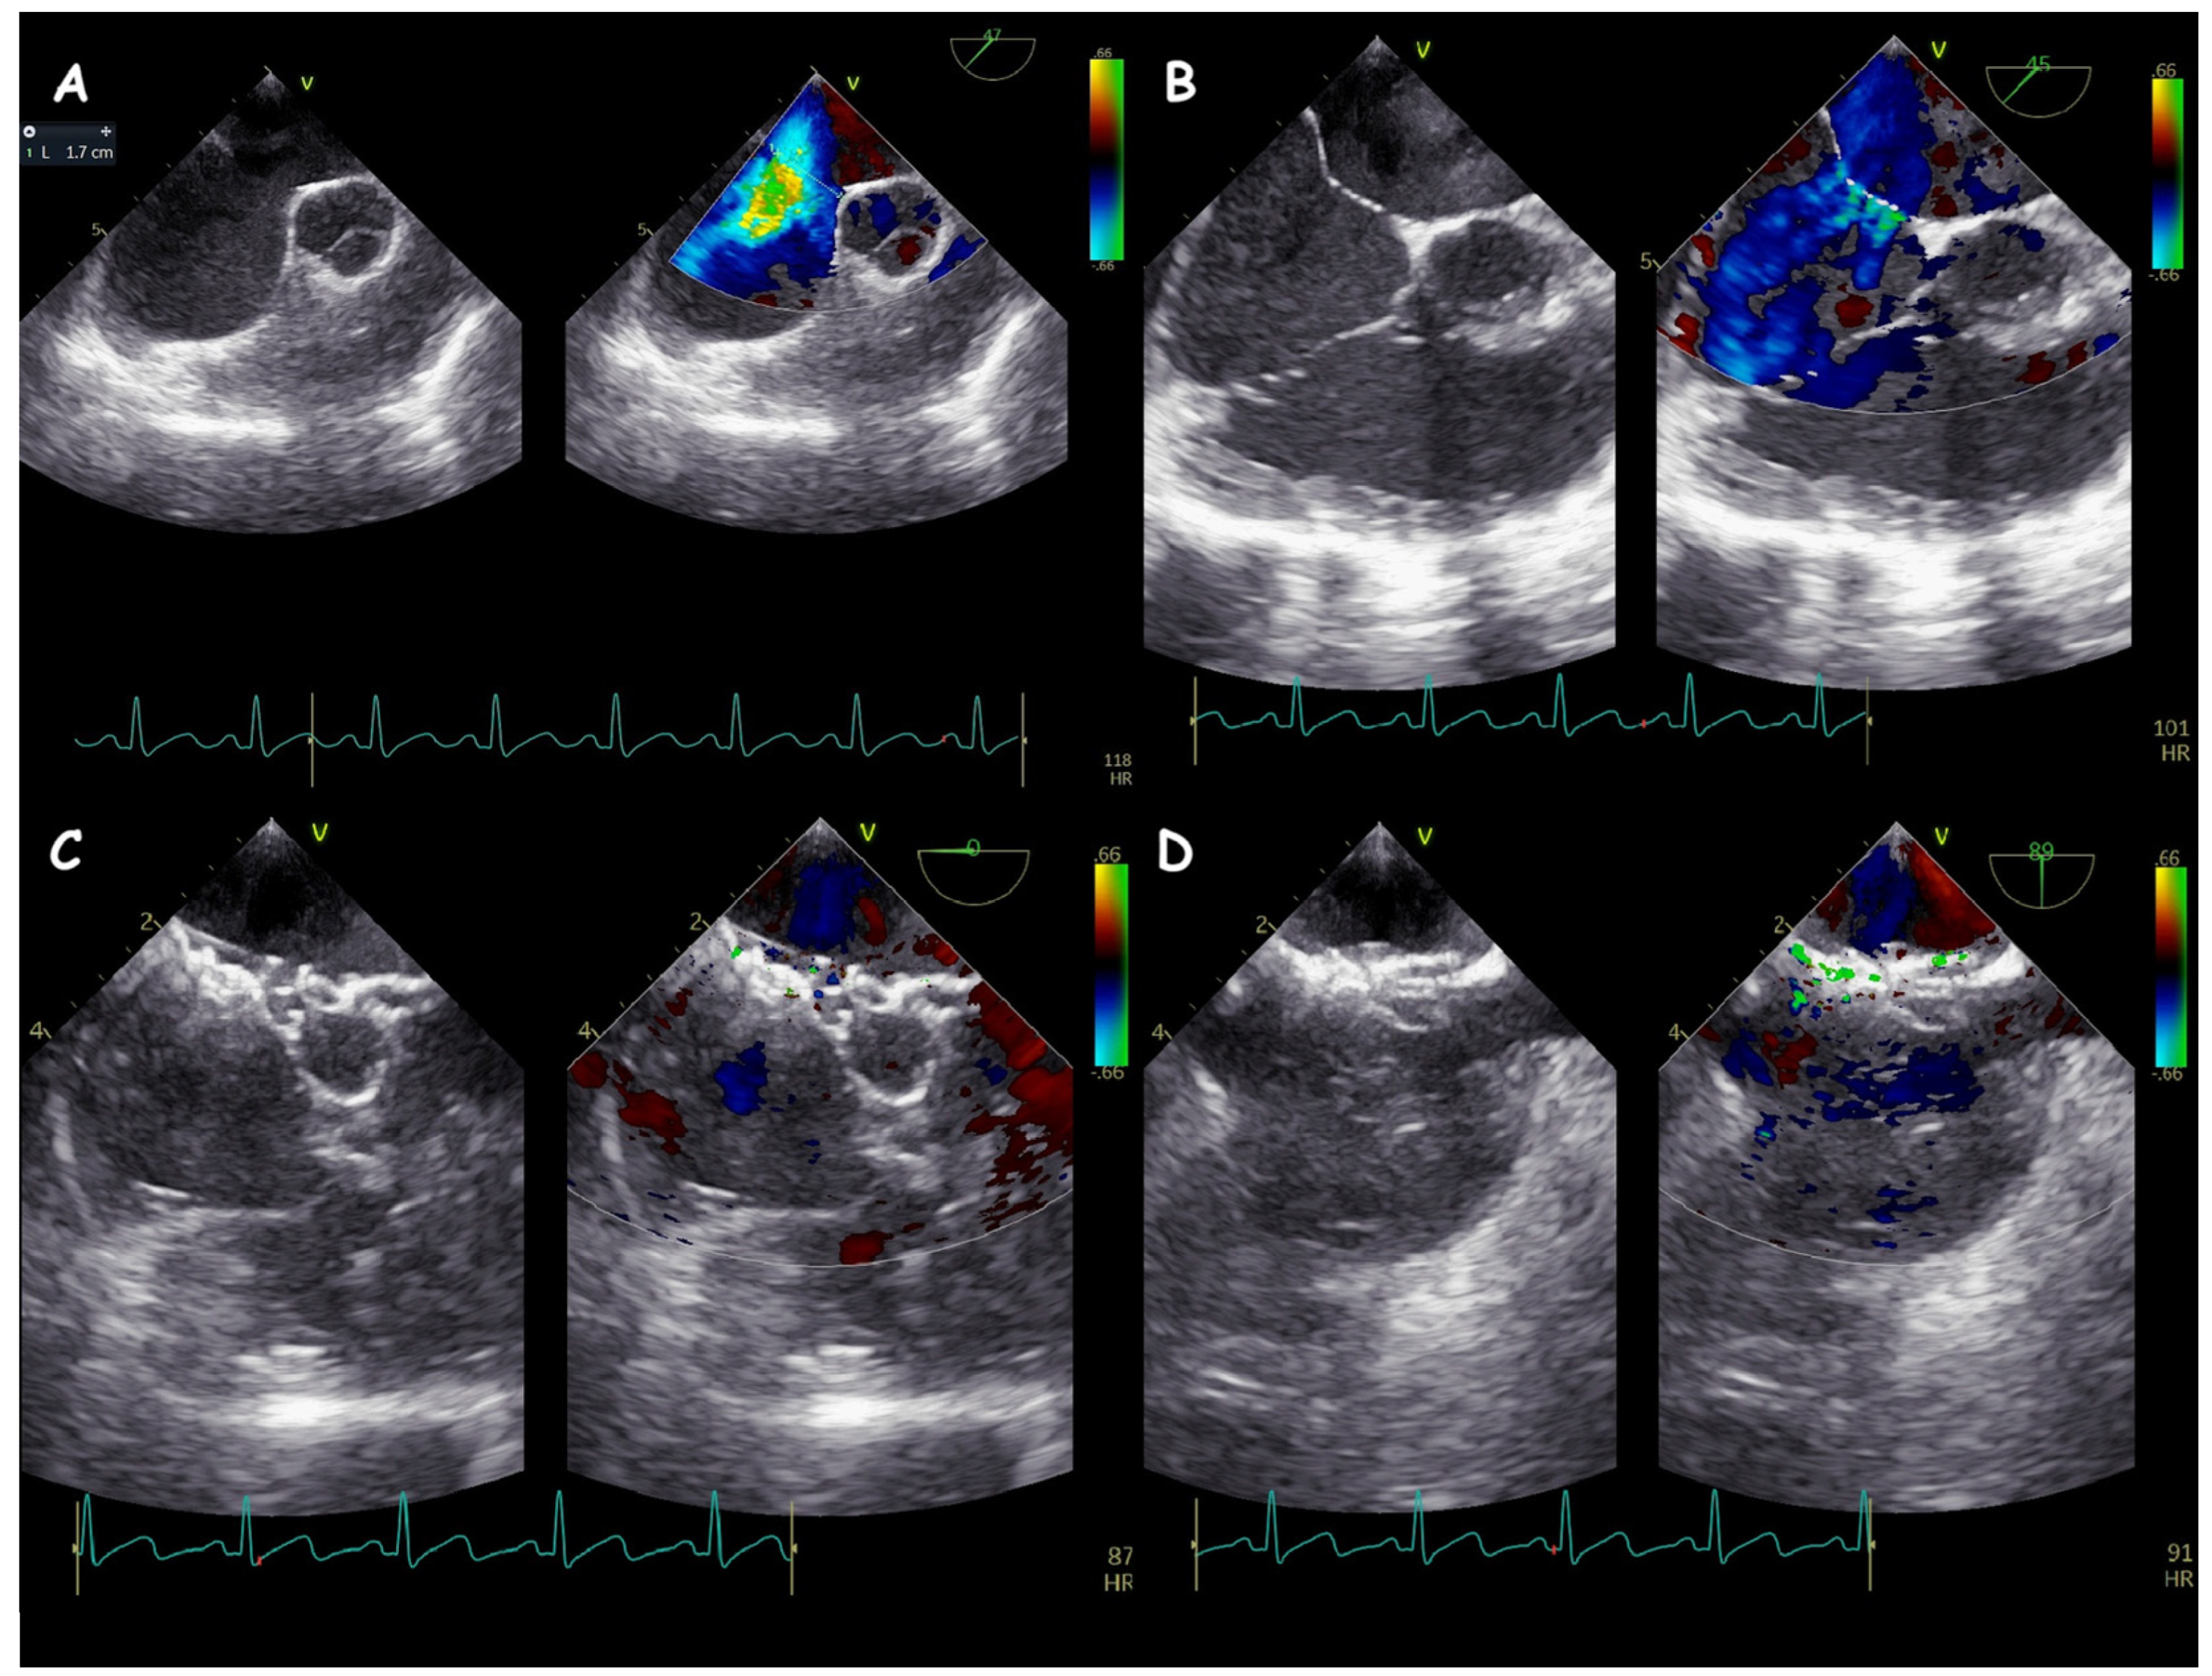

2. Atrial Septal Defect Closure

3. Ventricular Septal Defect Closure